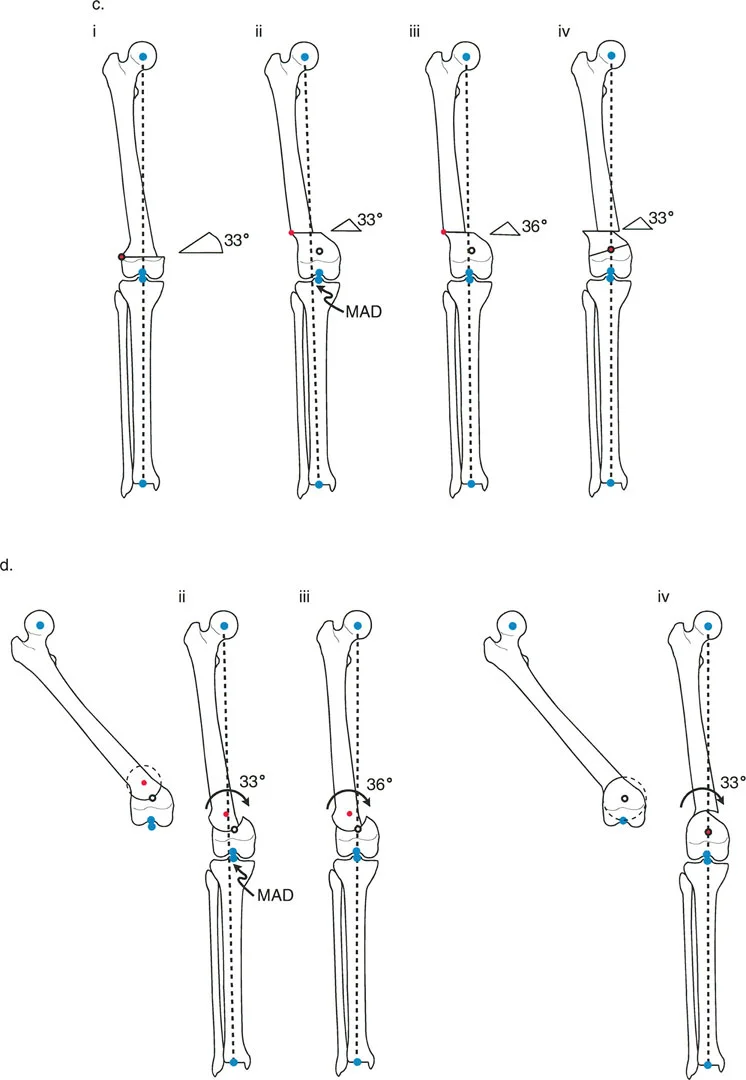

Paley Three Rules of Osteotomy

The cornerstone of frontal plane realignment lies in Paley's three osteotomy rules. Understanding these rules allows the surgeon to predict exactly how the mechanical axis, anatomic axis, and bone ends will shift upon correction. Mastery of these rules is what separates a master deformity surgeon from a novice.

Osteotomy Rule One Pure Angulation

The Geometric Definition

When the osteotomy line and the ACA both pass directly through the CORA, pure angular correction is achieved.

The Biomechanical Result

The mechanical axis is fully restored to normal. Because the bone is cut exactly at the apex of the deformity and hinged at that exact same apex, there is no translation of the bone segments. The anatomic axis realigns perfectly without any "step-off" or cortical bump. The proximal and distal bone segments will have maximum bony contact, promoting rapid union.

Clinical Application

This is the ideal surgical scenario. It is most easily achieved in diaphyseal deformities where the CORA lies in the midshaft, allowing the surgeon to safely cut exactly at the apex of the deformity. It is highly amenable to intramedullary nailing, as the re-established collinear anatomic axis allows for smooth passage of the guidewire and nail.

Osteotomy Rule Two Angulation with Translation

The Geometric Definition

When the ACA passes through the CORA, but the osteotomy line is made at a different level (either proximal or distal to the CORA).

The Biomechanical Result

The mechanical axis and joint orientation angles are perfectly restored. However, because the bone cut is made at a distance from the hinge point, the bone segments will mathematically translate relative to one another. This creates a visible "bump" or step-off in the anatomic axis. While the bone looks jagged on an x-ray, the load-bearing mechanical axis is flawless.

Clinical Application

Rule Two is frequently used for juxta-articular deformities. For example, if a patient has a severe distal femoral valgus deformity, the CORA may be located inside the knee joint. A surgeon cannot perform an osteotomy through the articular cartilage. Therefore, the surgeon must place the ACA at the joint (the true CORA) but perform the actual bone cut (osteotomy) safely in the metaphysis.

The resulting translation is not an error; it is a necessary and mathematically sound compromise to achieve a straight mechanical axis while cutting the bone in a biologically safe zone.

Osteotomy Rule Three Secondary Deformity

The Geometric Definition

When the osteotomy line and the ACA are both placed at a level different from the CORA.

The Biomechanical Result

A secondary translational deformity is created. While the angular deformity may appear to be corrected, the mechanical axis will not be fully restored. The proximal and distal mechanical axes will be parallel but not collinear, resulting in residual Mechanical Axis Deviation (MAD).

Clinical Application

In most cases, Rule Three represents an unintended surgical error. If a surgeon ignores the CORA and simply cuts the bone where it is most convenient, hiving it at the cut site, they will create a "golf club" deformity. The joint may be parallel to the floor, but the mechanical axis will be shifted, leading to rapid joint degeneration.

However, Rule Three can be used intentionally by master surgeons to correct pre-existing translational deformities. If a bone has a pre-existing translation, applying Rule Three can create an equal and opposite translation, effectively realigning the mechanical axis.

The Opening Wedge Osteotomy Sequence

An opening wedge osteotomy involves cutting the bone and pivoting the segments open, creating a triangular void. This void is usually filled with structural bone graft (autograft or allograft) or allowed to heal via distraction osteogenesis using an external fixator.

- Biomechanics and Limb Length The opening wedge inherently lengthens the limb. The ACA is placed on the convex side of the deformity (the side that acts as the hinge).

- Soft Tissue Implications Opening a wedge tensions the soft tissues on the concave side of the deformity. Surgeons must be hyper-aware of neurovascular structures. For example, a large medial opening wedge high tibial osteotomy (HTO) can stretch the superficial medial collateral ligament and potentially tether the peroneal nerve if not carefully managed.

- Rule 2 Dynamics in Opening Wedges If the osteotomy is proximal to the CORA, and the ACA is mistakenly placed at the osteotomy level rather than the CORA, an opening wedge will leave residual MAD. To eliminate this MAD, the surgeon might be tempted to overcorrect the angle, which unfortunately alters the joint orientation, causing joint obliquity. Therefore, strict adherence to placing the ACA at the CORA is mandatory.

The Closing Wedge Osteotomy Sequence

A closing wedge osteotomy involves removing a predefined triangular wedge of bone and bringing the two flat bony surfaces together.

- Biomechanics and Limb Length The closing wedge inherently shortens the limb. The ACA is placed on the concave side of the deformity.

- Soft Tissue Implications Closing a wedge slackens the soft tissues on the convex side. This is highly advantageous when neurovascular tension is a concern, or when the patient already has a limb length discrepancy where the deformed limb is longer.

- Surgical Execution Closing wedges require precise preoperative templating. The surgeon must calculate the exact base of the wedge in millimeters to achieve the desired angular correction. Once the bone is removed, the broad cancellous surfaces provide excellent bone-to-bone contact, leading to high union rates and inherent stability, making it ideal for internal fixation with plates and screws.

The Dome Osteotomy Sequence

A dome (or focal dome) osteotomy utilizes a cylindrical or spherical cut rather than a straight transverse cut.

- Biomechanics and Limb Length The true advantage of a dome osteotomy is that it allows for pure rotation of the bone segments without altering limb length and without creating a prominent cortical step-off, even when applying Rule 2.

- Geometric Execution To execute a perfect dome osteotomy, the center of the dome's radius of curvature must be exactly at the CORA. The ACA is also placed at the CORA. As the bone segments slide along the curved cut, the mechanical axis is restored.

- Clinical Application Dome osteotomies are technically demanding and require specialized crescentic saw blades or a drill-hole technique. They are highly favored in the metaphyseal regions (like the proximal tibia or distal femur) where maintaining maximum bone contact and avoiding limb shortening is paramount.